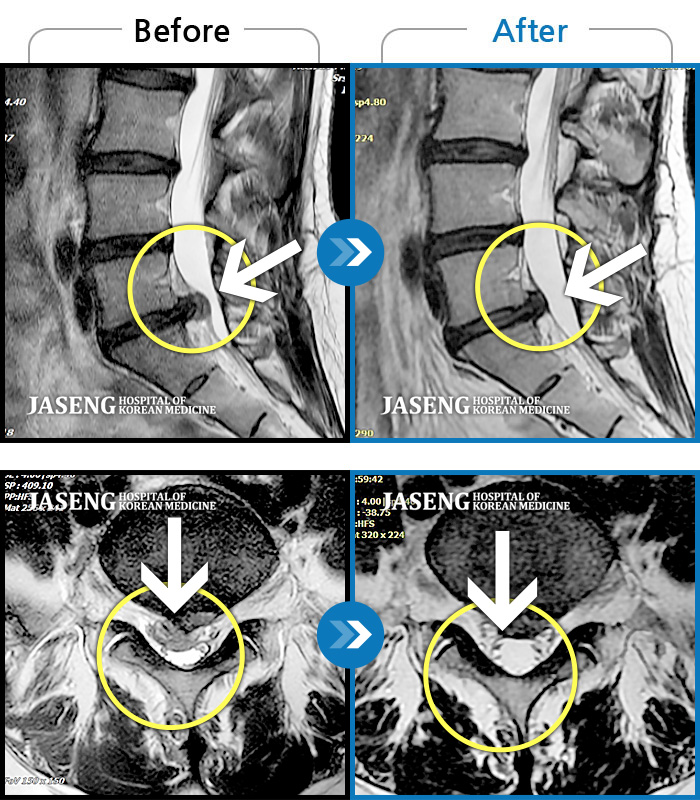

MRI 치료사례

우측 허리와 골반 통증, 우측 다리에 통증과 저림